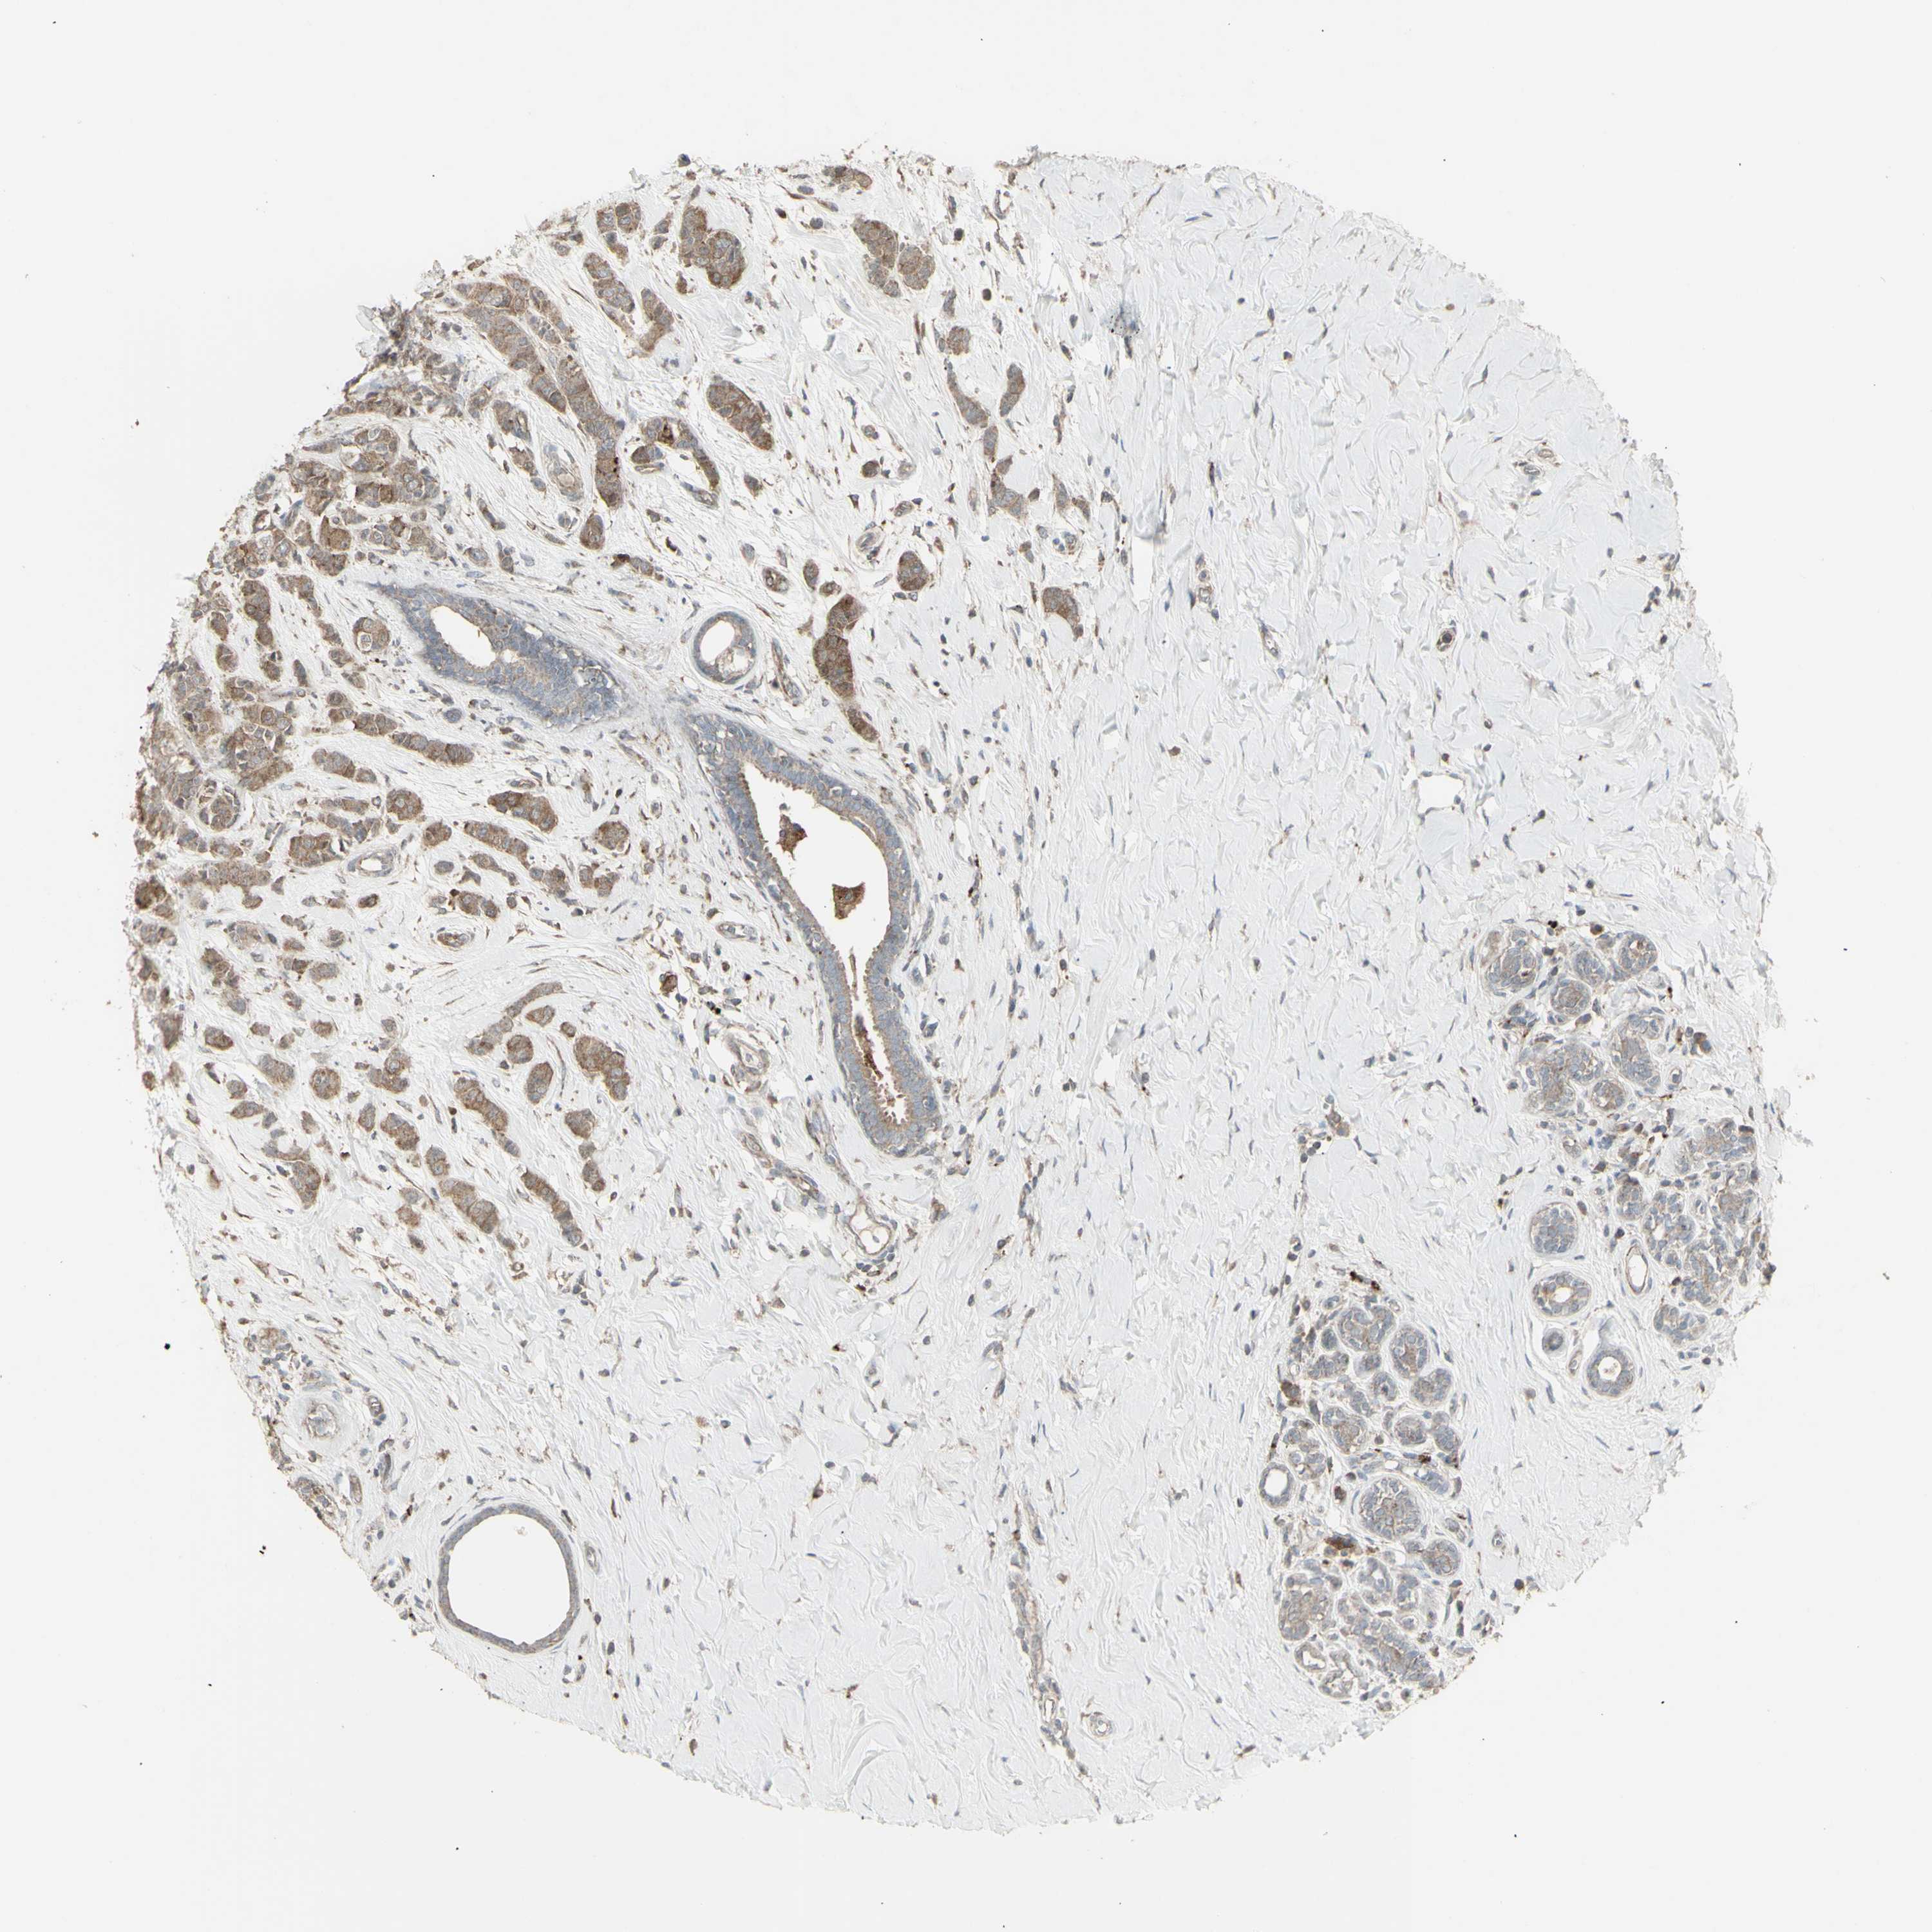

BRCA TCGA BRCA VALIDATION PROTEIN EXPRESSION

ANTIBODIES

AND

VALIDATION